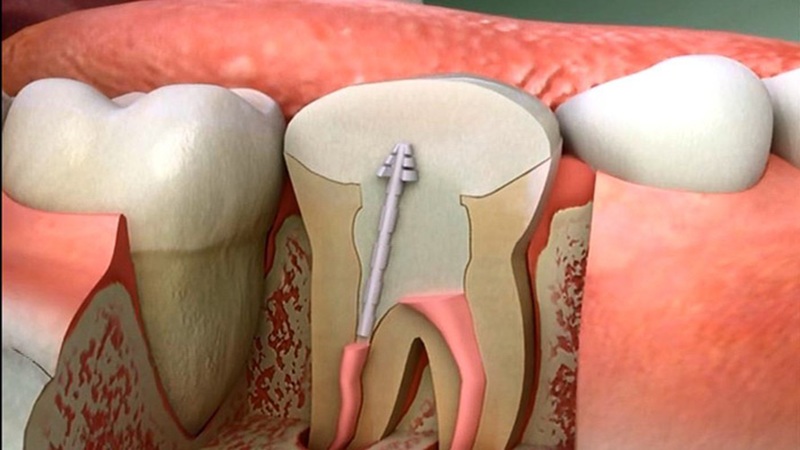

درمان ریشه یکی از درمانهایی است که نام آن برای بسیاری از بیماران همراه با تصور درد و اضطراب بوده است. اما با پیشرفت تکنولوژیهای دندانپزشکی، این باور در حال تغییر است. امروزه درمان ریشه نهتنها یکی از قطعیترین روشهای نجات دندان است، بلکه اغلب بدون درد و با حداقل ناراحتی انجام میشود. در این مقاله از سایت دکتر حسین برجیان (بهترین دندانپزشک اصفهان _ بهترین جراح لیفت لثه اصفهان)، درد درمان ریشه دندان را بررسی میکنیم.

بیمار در حین درمان به کمک بیحسی موضعی پیشرفته، هیچ دردی حس نمیکند. ابزارهای جدید و فایلهای ظریف، امکان پاکسازی دقیق را فراهم کرده و روند درمان سریعتر و کماسترستر شده است.

درمان ریشه با لیزر یکی از پیشرفتهترین تکنیکهاست که به شکل قابل توجهی درد و التهاب را کاهش میدهد.

* ضدعفونی عمیق و قطعی کانالها

درمان ریشه برخلاف تصور عمومی، یکی از کمدردترین روشهای درمان دندان در دندانپزشکی مدرن است. درد شدید معمولاً مربوط به عفونت قبل از درمان است و نه خود فرآیند. با بیحسی پیشرفته، لیزر و ابزار دقیق، تجربه بیمار امروز بیشتر شبیه یک درمان معمولی و بدون استرس است. با انتخاب متخصص باتجربه و رعایت مراقبتهای پس از درمان، میتوان بدون نگرانی از درد، دندان را نجات داد و سلامت آن را برای سالها حفظ کرد.